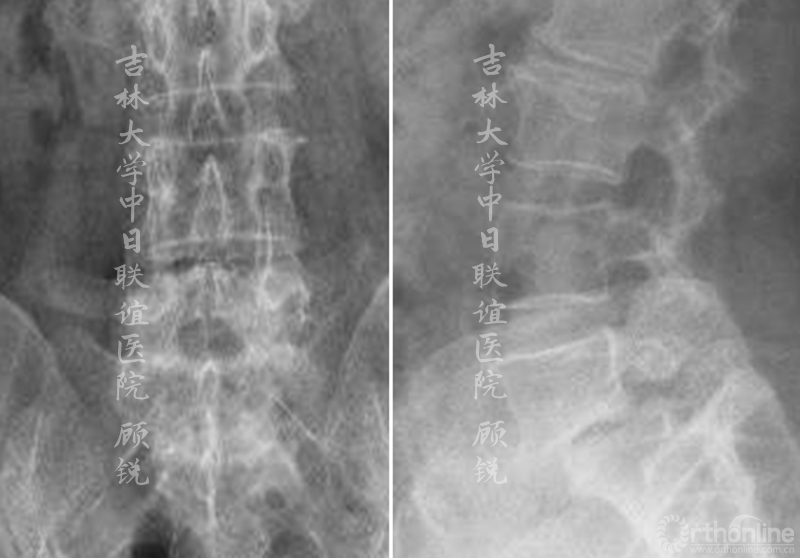

术前X线:

腰椎CT:

(L5-S1)